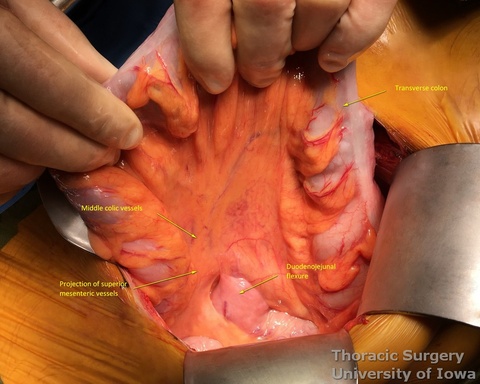

- The site for the feeding jejunostomy is located 20 cm distal to the duodenojejunal flexure (commonly and inaccurately called "ligament of Treitz", which is located in the retroperitoneum and is not visible)

- 16 Fr feeding Witzel (KP, EA) or Stamm (JK) or jejunostomy is placed (see: Witzel feeding jejunostomy)